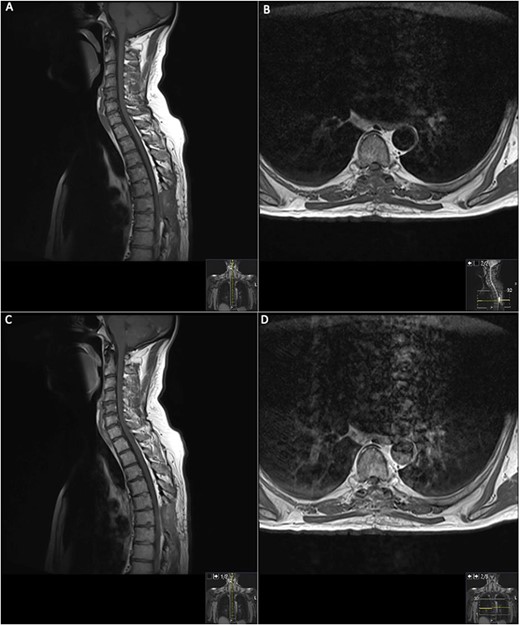

The patient was started on methylprednisolone (1 g/day) for 3 days under the neurology team; however, this did not improve his neurological status, and subsequently, his neurology progressively worsened to a lower limb weakness to an MRC grade of 1/5 bilaterally with faecal incontinence. A second MRI spine was performed with contrast (Fig. 2).

Repeat contrasted MRI whole spine; demonstrates findings consistent with spinal cord meningioma at the level of T6; this can be clearly visualized by comparing the T1 sagittal pre-contrast (A) with a T1 sagittal post-contrast (B), where a clearly demarcated lesion can be seen at the level of T6; this is supported further by the sagittal T2 image (C) shown where an ~24 mm lesion can be seen at T6.